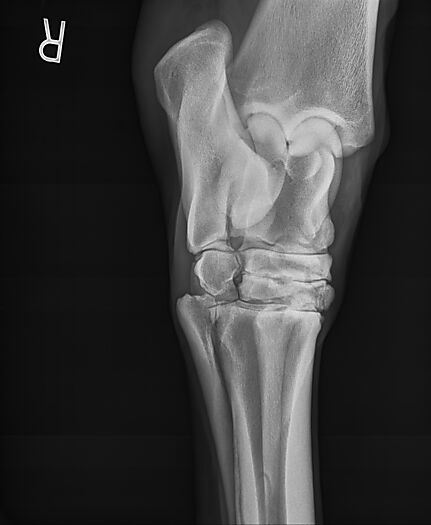

**Tex sells at the Colorado Horse Sale's Best of the West Select Sale on May 30th in Castle Rock, CO - He will complete the riding & handling Sift Exam, baseline veterinary exam, and will sell with 4 total radiographs (DLPMO & Front Foot Lateral)**